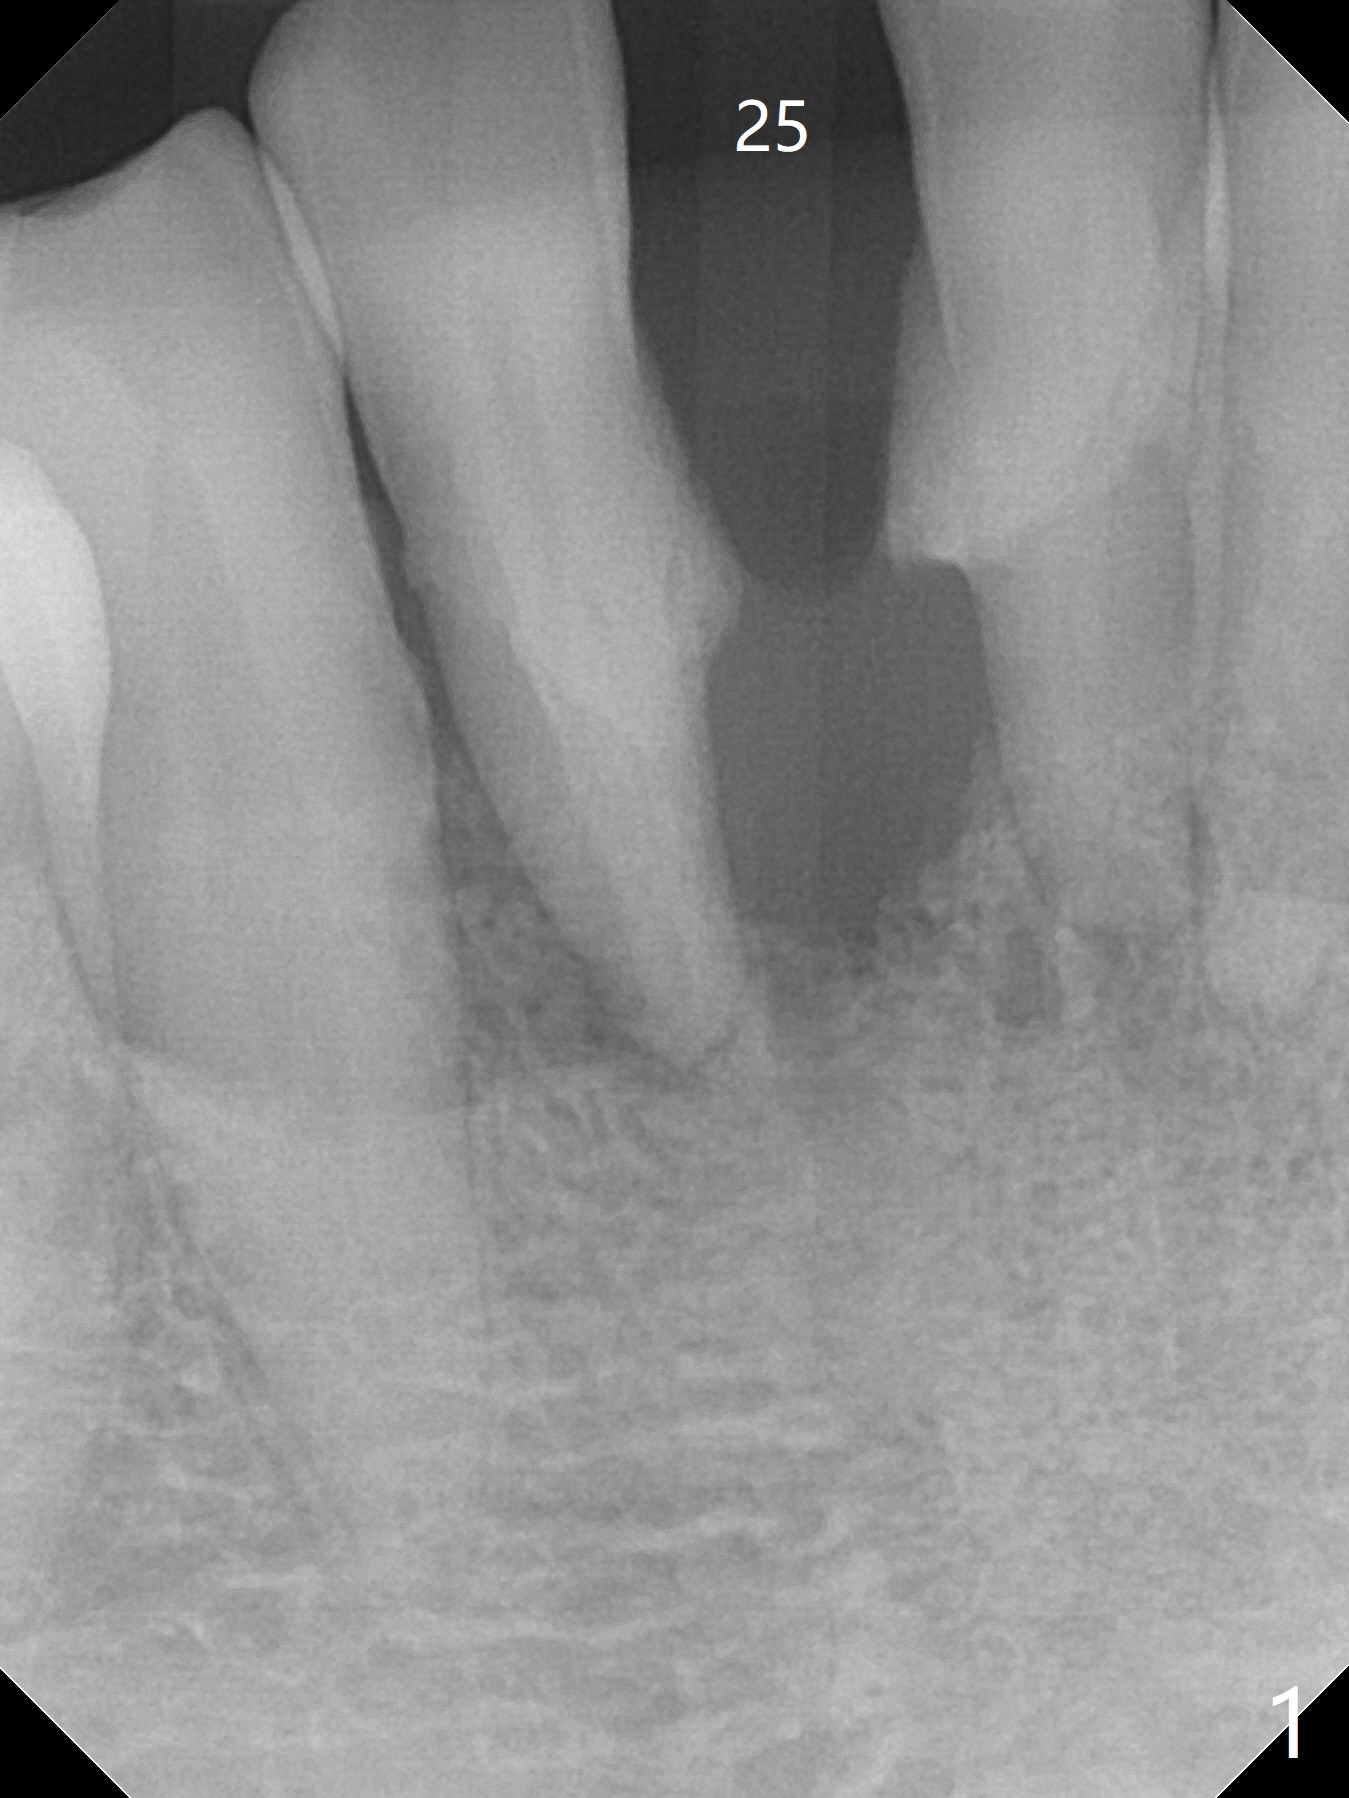

A 56-year-old man is a dental phobic. He finally seeks treatment because of loss of the tooth #25 with air leakage during speech (Fig.1). If the remaining lower incisors are stable after scaling and root planing, a 2.5 or 2.0 mm 1-piece implant will be placed in the narrow edentulous space (Fig.2). The implant driver (green sleeve) may touch the neighboring teeth, which need adjustment. If the worst incisor (#26 tender prior to SRP) is deemed to be non-salvageable, a 2.5 mm implant will be placed with a cantilever 2-unit FPD (Fig.3). If the tooth #23 is a survivor, two of 2.5 or 2.0 implants will be placed at #24 and 26 with a subsequent FPD (Fig.4). If the remaining incisors are all questionable in prognosis, two implants will be placed in the ends with a FPD (Fig.5). After SRP, the tooth #26 is less tender; the patient is ok with its extraction, but insists on saving #23 and 24. If 2 implants are to be placed at #25 and 26, they need to be 2 mm in diameter (Fig.6) with risks of injuring the neighboring teeth. It appears that it is more reasonable to have a single implant, slightly larger (2.5 or 3 mm), at #26, with the coronal end slightly mesial (Fig.7) with a cantilever bridge. If the teeth #23 and 24 fail in the future, a normal one will be easily converted.